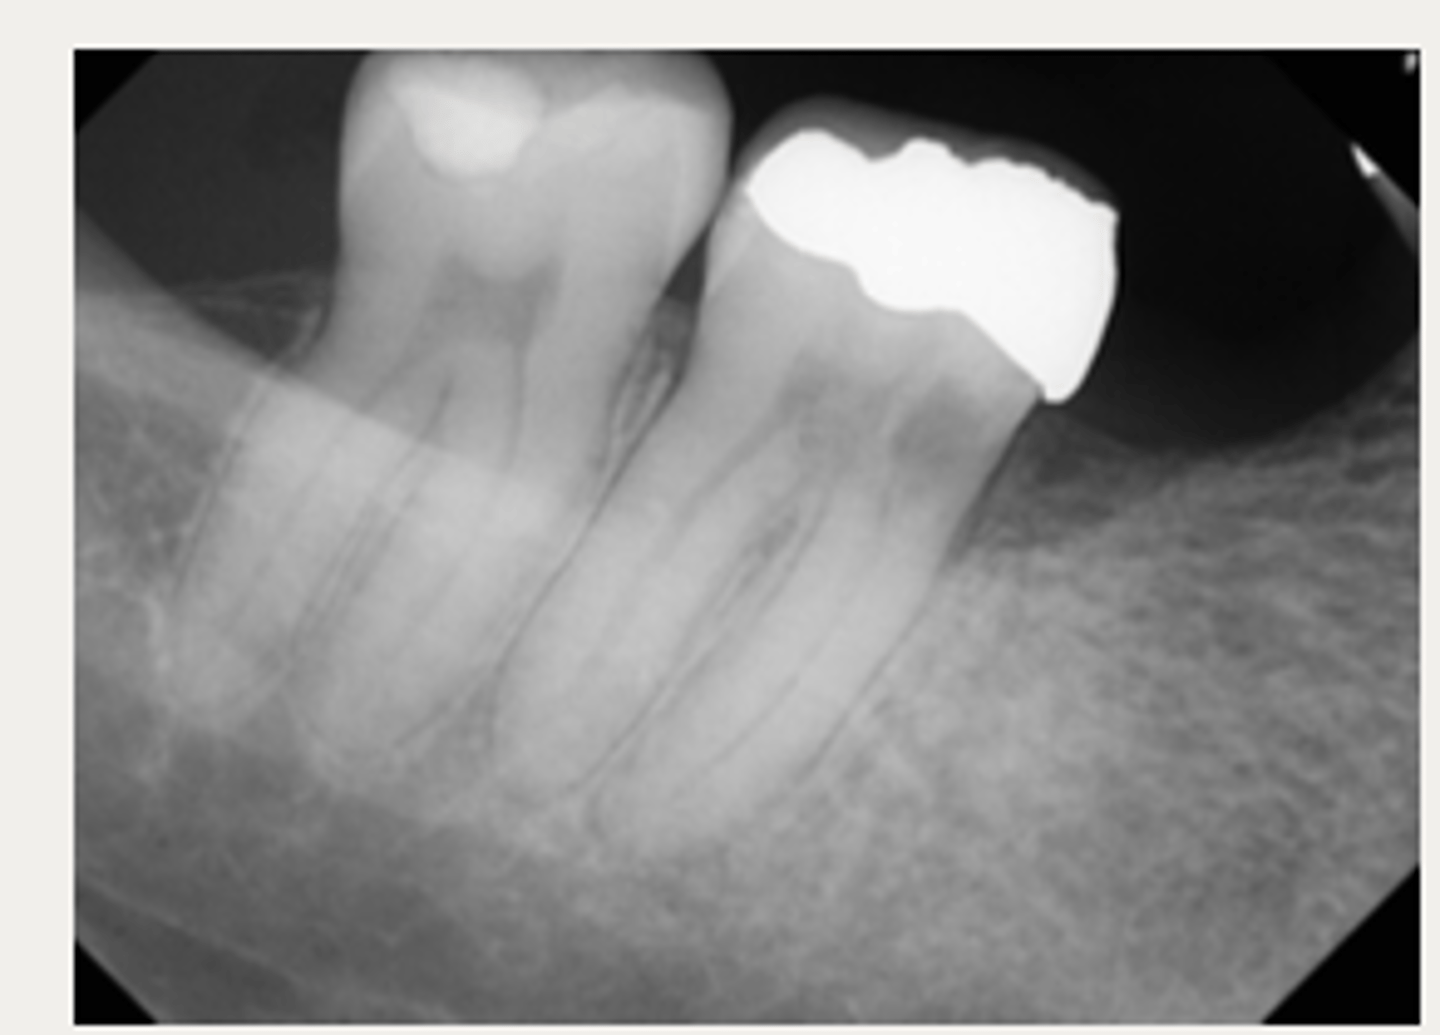

External cervical resorption (Invasive Cervical Resorption)

ID the type of resorption:

- Usually an incidental radiographic finding, especially for less advanced lesions

- Variable appearances; may be a well-defined or irregular radiolucency around the cervical aspect of the tooth

- A portal of entry is always present in the cervical region of the tooth

- The chamber/canal outline is often visible as the innermost layer of predentin around the chamber is not resorbed

Patient presents with these radiographic findings, what type of resorption?

- Incidental finding

- Radiolucency around cervical aspect of tooth

- Portal of entry present in cervical region

- Chamber/canal outline is visible